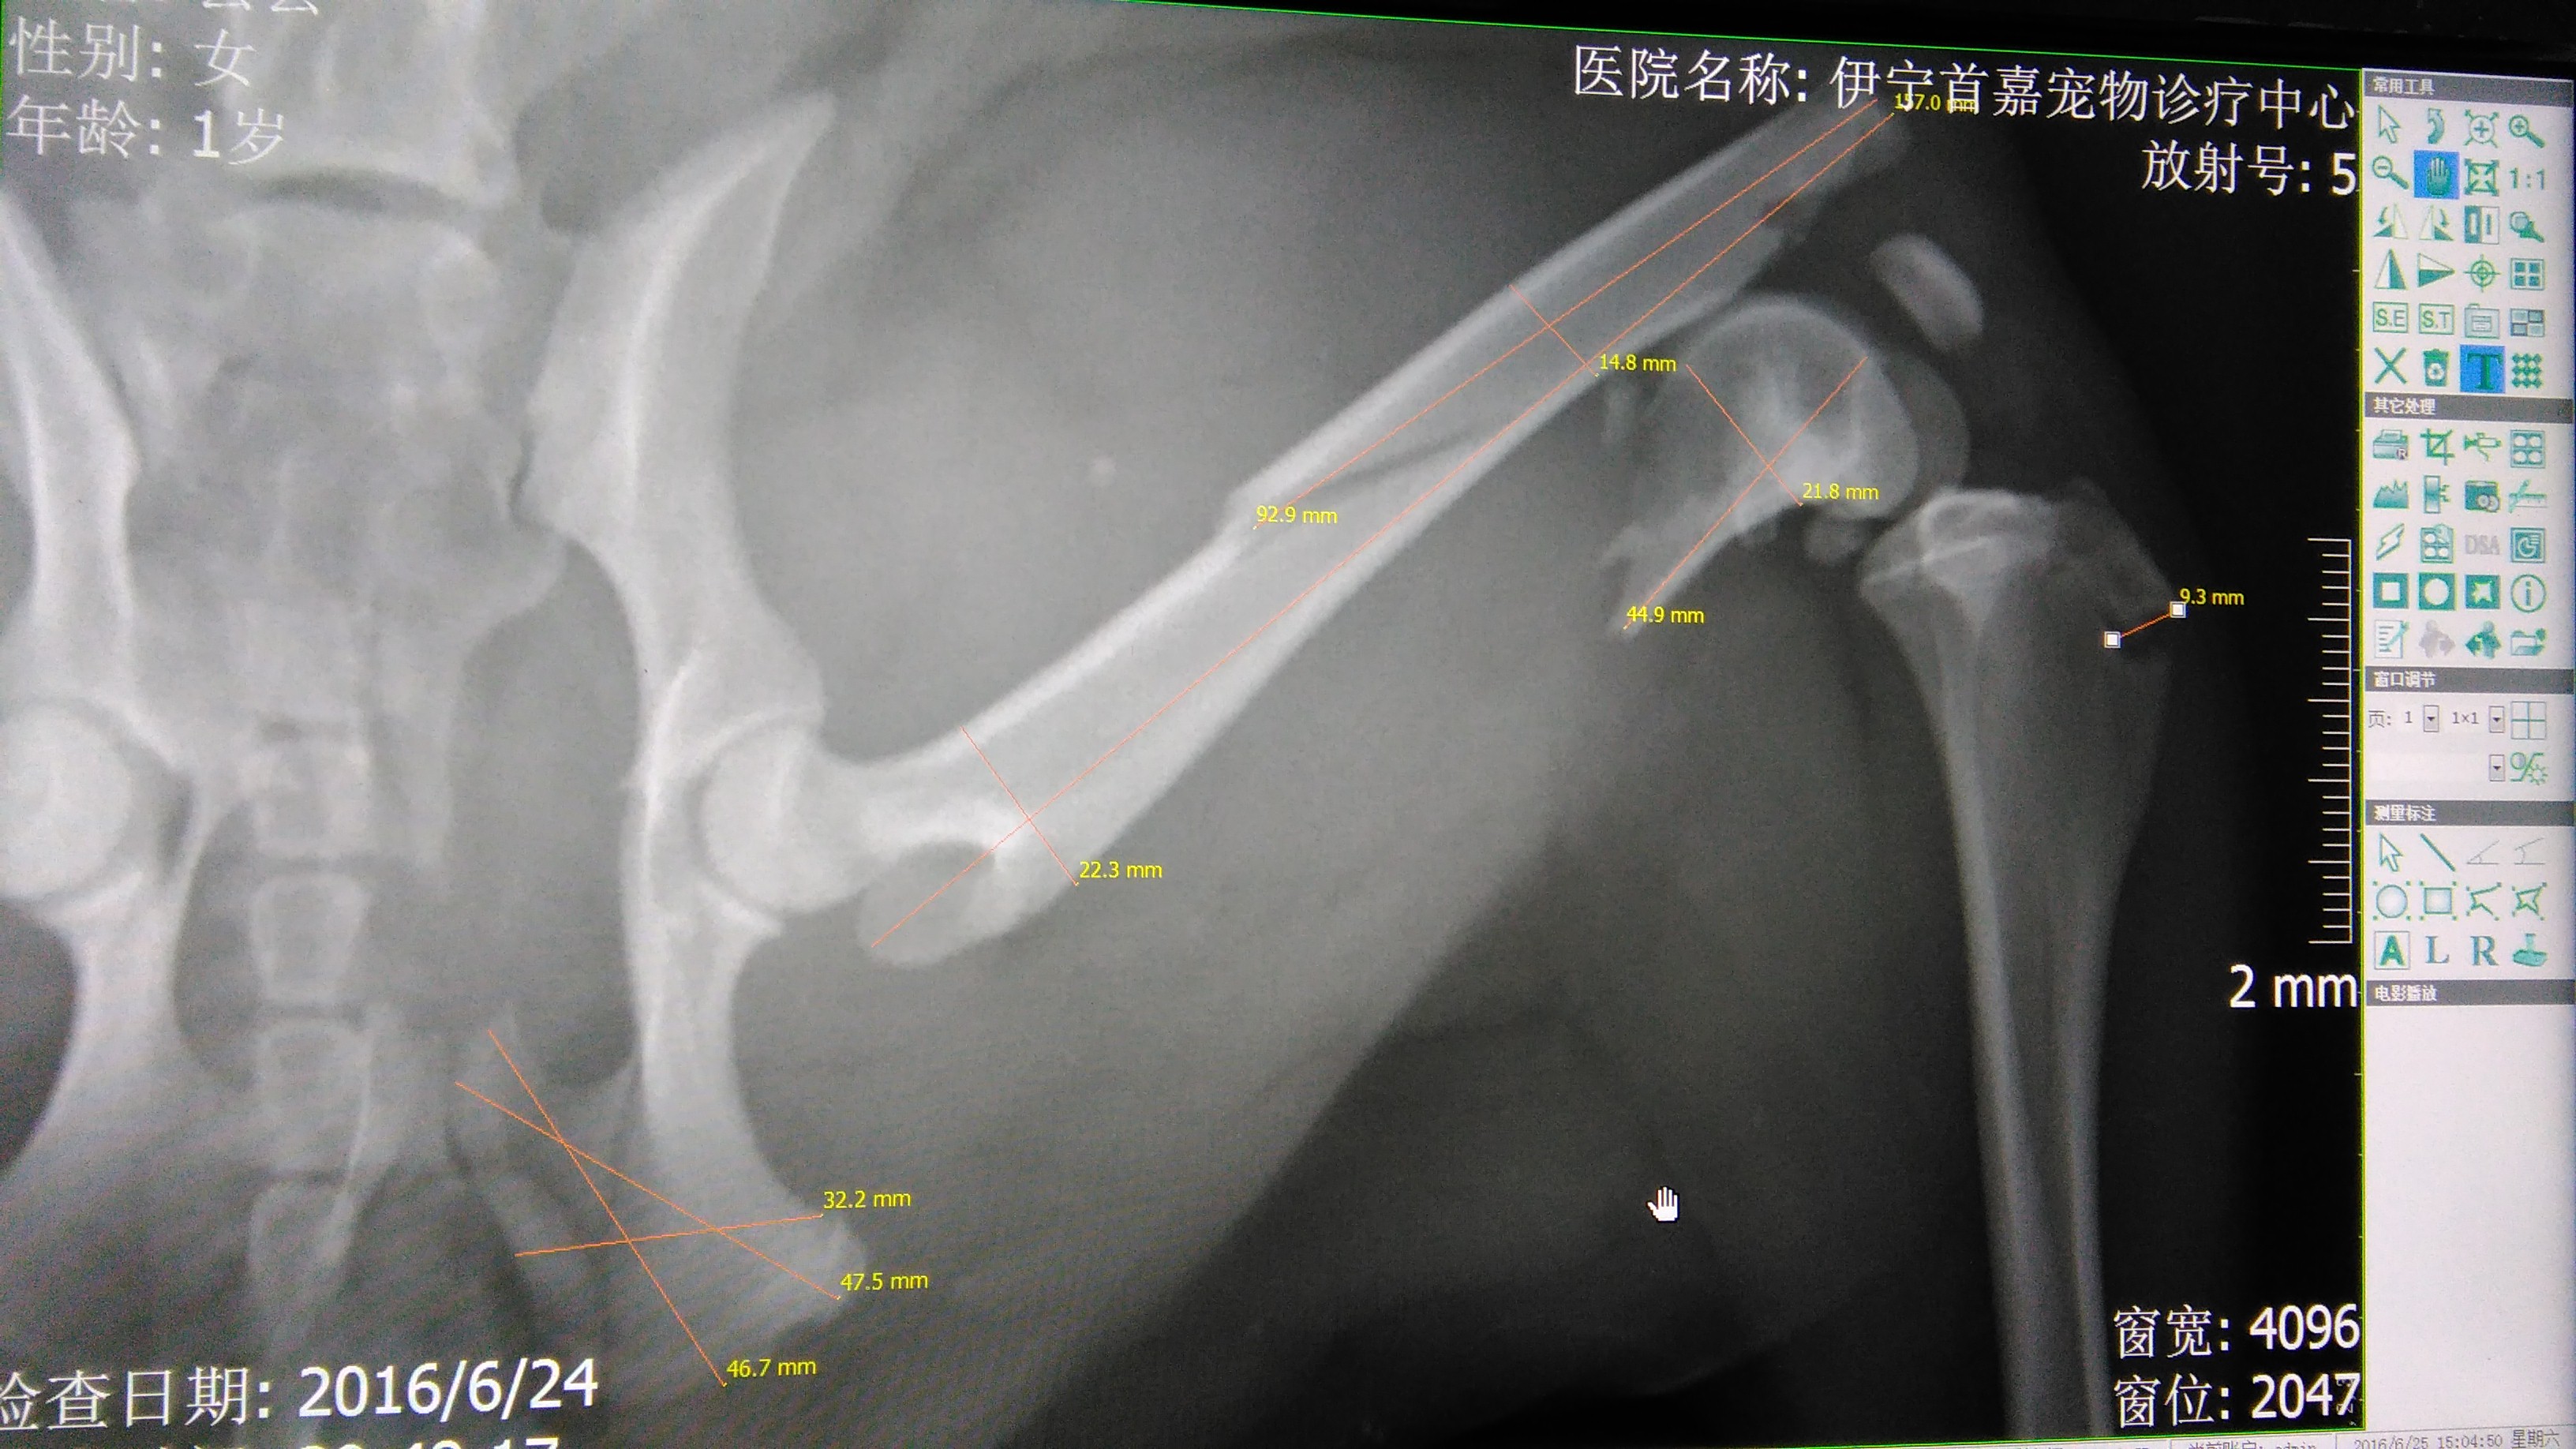

金毛犬,丢丢。于2016年6月24日晚车祸送到我院治疗,检查完之后,肝脏破裂出血,左后腿粉碎性骨折,断成三阶。第二天主人因经济问题放弃治疗,我院接手她,并有大量爱心人士捐款治疗。前期一直在调理修复肝脏和内出血治疗中,7月6号进行骨折内固定手术,手术中发现股骨断端撕裂膝关节并导致韧带断裂,手术修复并固定。经过一段时间调养,丢丢又可以走路。